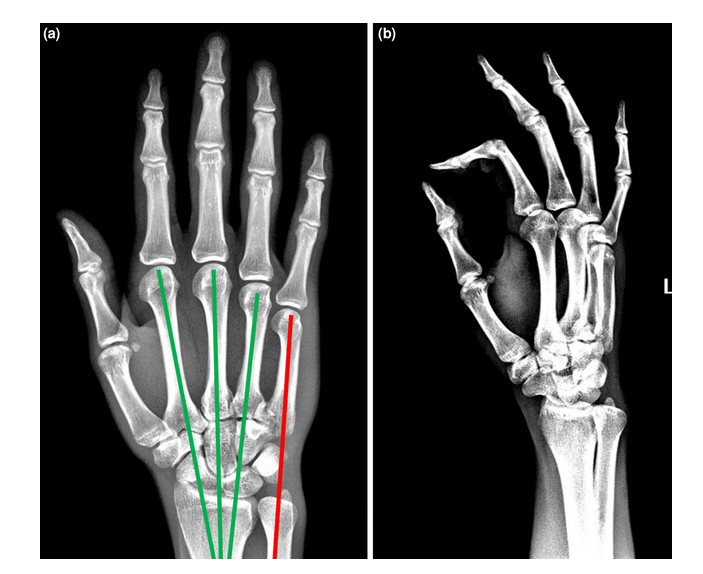

手术患者术前和术后的x线图像。(a)掌骨级联线AP x线。这些线沿着掌骨的轴线画;绿色表示解剖性,红色表示脱位,因为它不与其他关节相交。(b)术前斜位x线片。